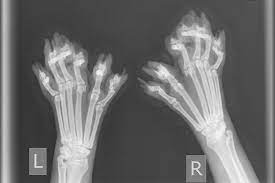

Legg merke til kloen midt under poten.

Hultertilbulter og lite vakkert.

Ser dette behagelig ut?

Når putene og klør ligger “hultertilbulter” på poten, hvordan oppleves dette for katten?, har de leddsmerter, muskel eller nerve ubehag. Katten skal tross alt gå på disse potene gjennom hele livet. Vet vi at katten gjennom hele livet vil ha smertefrie poter?

– Leddene kan være vridde, noe som kan være smertefullt

– Om det ikke er plass til kattens ekstra tær “former de seg til plassen”, noe som kan gi skjeve ledd.